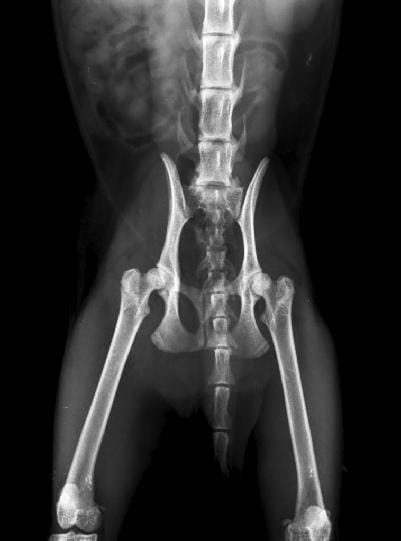

Artrosis en gatita de año y medio

A mi gata de año y medio le han diagnosticado artrosis de cadera y artrosis de codo, también fue diagnosticada con calicivirus hace unos meses. El veterinario que la ha diagnosticado nos aconseja que NO la operemos, y nos recomienda dos opciones de tratamiento: aplicar factores de crecimiento o trasplante de células madre.

El pronóstico que nos ha dado no es demasiado bueno, puesto que el codo izquierdo ya está en bastante mal estado como se ve en las radiografías y las caderas van por el mismo camino, sobretodo la derecha. Además nos comentó que el calicivirus va a hacer que se deteriore todo más rápido.